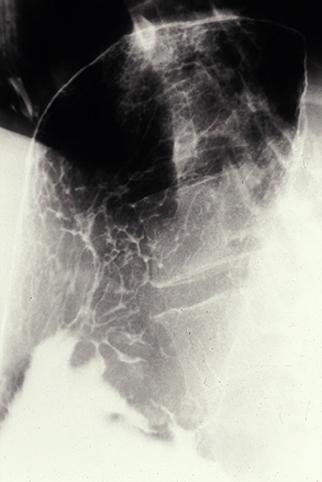

A case of so-called early gastric malignant lymphoma which characteristically showed various features.

[ Image ID:9128 ]

Criteria of Hist.Classification

Malignant Lymphoma/Malignant lymphoma

Location

Stomach/More than one of above

Technique, Method

X-ray

Size

40 -

Depth of Tumor Invasion

submucosa